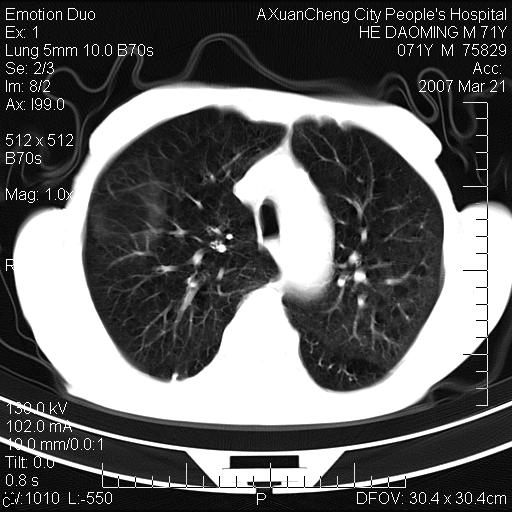

1.慢支肺气肿 肺心病 肺大泡;2.叶间裂积液,前胸膜粘连

考虑:慢性支气管炎合并全小型肺气肿、肺大泡、间质纤维化、感染,右斜裂积液。

考虑:慢性支气管炎合并全小型肺气肿、肺大泡、间质纤维化、感染,右斜裂积液. 冠状动脉硬化(冠心病)

考虑慢支,肺气肿,肺大泡,间质纤维化;右侧斜裂液气胸考虑(可能因为肺大泡破裂破入斜裂所致).

考虑病变以右上中肺多发肺大泡为主并感染。请结合临床考虑慢支肺气肿,肺心病。

1双肺慢性支气管炎并全小叶型肺气肿肺大泡2间质性纤维化3右侧斜裂积液

考虑:慢性支气管炎合并右侧全小型肺气肿、肺大泡并感染、双肺间质纤维化,右斜裂积液。